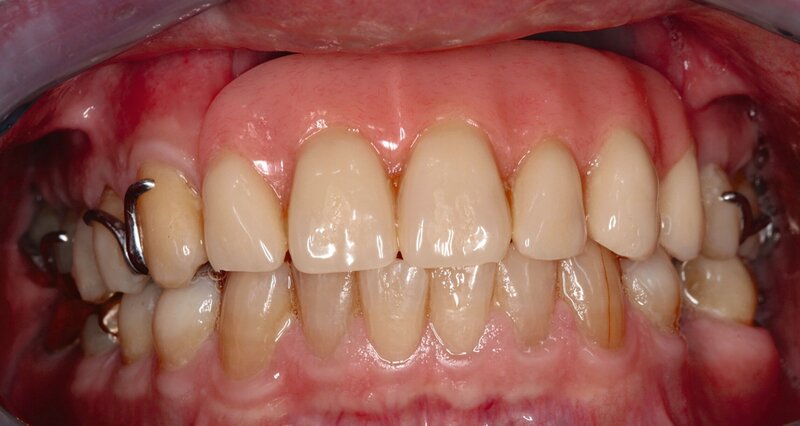

Bei einer Obturator-Prothese (Abbildung 2) erfolgt der Defektverschluss mittels hartem Acrylat-Prothesenkunststoff. Sie kann im Zenit offen oder geschlossen gestaltet sein. Der Halt wird über Klammern, Teleskope oder eine implantatgetragene Verankerung erzielt. Bei vollständiger Zahnlosigkeit ist eine Obturator-Prothese nicht zu empfehlen, da der gewöhnlich genutzte Saugeffekt nicht hergestellt werden kann. Bei zahnlosen Patienten, die keine Implantate erhalten können oder sollen, ist es sogar empfehlenswert, den Defekt nicht zu rekonstruieren, damit Unterschnitte für einen Silikon-Obturator genutzt werden können.

Die Handhabung und Reinigung einer Obturator-Prothese ist selbst bei kompromittiertem Geschick einfach und eine Unterfütterung ist wie bei einer herkömmlichen Prothese gut durchzuführen. Zu bedenken ist hier, dass der Patient funktionell stark eingeschränkt wird, wenn die Prothese im zahntechnischen Labor angepasst werden muss. Bei ausgedehnten Defekten kann eine Obturator-Prothese sehr groß werden. Dies erschwert bei eingeschränkter Mundöffnung oft die Eingliederung, weshalb hier gegebenenfalls geteilt werden muss. Eine Verbindung der Einzelteile kann über Riegel, Zapfen oder Magnete erfolgen. Bei bestrahlten Tumorpatienten ist das Entstehen von Druckstellen durch die Nutzung eines harten Prothesenkunstoffs ein Risiko, das beachtet werden muss.